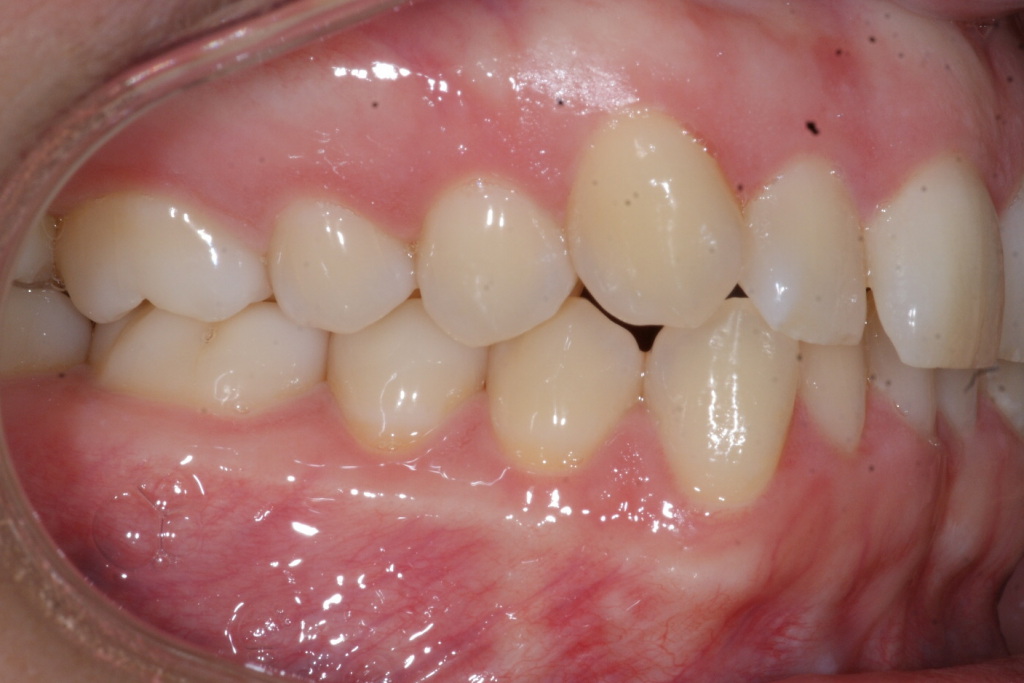

Correction d’une malocclusion de type Classe I, surplombs inadéquats et chevauchement modéré aux 2 arcades.  57 coquilles furent nécessaires pour améliorer ce sourire.  Traitement chez une adulte, réalisé en 15 mois.